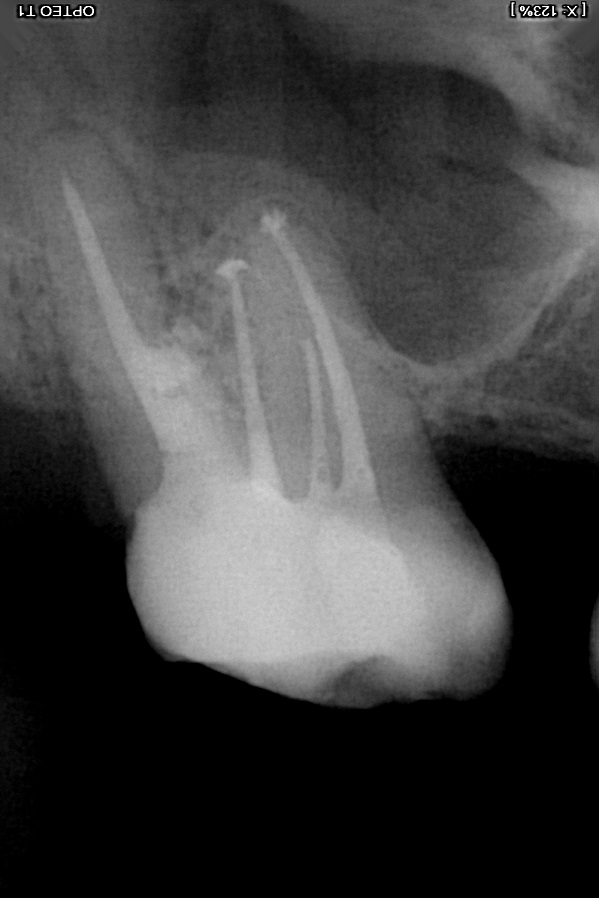

Beste Tandartsen. ik heb een kies die 10 jaar gelden een wkb heeft gehad bij een endodontoloog nog.

de kies was altijd nog wat gevoelig zwakke kies maar met kauwen geen problemen.

meestal kreeg ik last in het voorjaar van kiespijn .en de tandarts maar foto's maken en zag jaren niks. nu een week geleden ineens erge last van mijn kaak aan de kant waar de kies zich bevind. trok met steken in het voorhoofd ook had ik bloed in het neusgat aan de kant van de kies. het andere neusgat dus niet. .voelde mij echt niet lekker. leken wel aanvallen want daarna ging het telkens weer wat beter en zakte het weer. bij warm eten klaarde het vreemd genoeg helemaal op dat gaf verlichting. ik zit nu een week aan de Naproxen en het is nu weer stabiel. maar ik had weken ervoor al veel last van mijn buik gehad. ineens ook pijnsteken in de buikstreek en maag. wist niet waardoor dacht misschien een virus ofzo en dat het dan nu overgesprongen was naar mijn kaak.. ben een keer een maand geleden naar de huisarts voor de buikklachten geweest . die dacht omdat ik melk dronk het daar aan lag maar bleek dus achteraf niet zo te zijn geen last meer van en drink gewoon elke dag mijn melk.

afijn vanmiddag naar de tandarts geweest en op de foto zag de tandarts ineens dan mijn wortel was opgelost. ze voelde ook met een haakje en had daar aan de achterkant wel wat diepe pockets. ze dacht aan een breuk in de wortel maar ik heb geen last met kauwen erop. alleen als ik met mijn tong op het kaakbot achter de kies druk dan voel ik wat. .

ik heb even een foto erbij voor Tandarts Richard .wat kunt u concluderen aan de hand van deze foto?

Ik had het met mijn tandarts al over het plaatsen van een implantaat gehad. dit wilde ik eigenlijk 10 jaar geleden al toen ik last van deze kies had maar toch naar een endodontoloog ben gegaan voor herbehandeling nadat mijn tandarts de wortel perforeerde bij her behandeling omdat hij deze maar voor de helft gevuld had met kanaalvulling. de wortel die nu dus aan het verdwijnen is. ik weet niet hoe dit verdwijnen komt na 10 jaar maar weet wel dat de boor tijdens de het perforeren destijds met een klap vastsloeg in deze wortel. kan dat er iets mee te maken hebben?? maar waarom dan pas 10 jaar later vraag ik mij af? of is dit een proces van 10 jaar? de endodontoloog heeft de perforatie toen met MTA gedicht. ze was erg positief erover.

eigenlijk had de tandarts dit gat al gelijk moeten dichten maar die had geen microscoop en wilde de kies niet meer aanraken. ik zie wel op de foto waar de wortel onderbroken is precies zit waar de kies in het verleden is geperforeerd. zie andere foto van direct na de endo 10 jaar geleden.